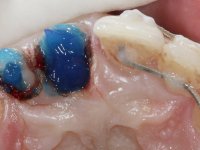

Foi feito o tratamento endodôntico dos dentes 2.1 e 2.2.de imediato, a sintomatologia que o paciente manifestava a isso impunha. Na mesma consulta foi realizada uma extensa gengivetomia com o bisturi elétrico, no sentido de expor os limites cervicais da fratura. Foram colocadas resinas compostas nos remanescentes radiculares com a intenção de reformular a emergência dos tecidos moles. Realizei a impressão dos remanescentes radiculares para confeção em laboratório de uma ponte provisória. A ponte provisória de 2 elementos, apresentava um formato que visava no futuro acomodar o coto dos espigões falsos cotos que iria ser cimentados nos remanescentes radiculares. Apresentava um reforço metálico palatino e dois apoios para os dentes adjacentes, um mesial e outro distal. Os remanescentes radiculares foram preparados para a confeção de dois espigões falso coto fundidos. As linhas de acabamento cervical foram definidas e os canais radiculares desobturados e preparados. A impressão foi realizada com a utilização de tutores de plástico com a técnica de dupla mistura. O afastamento gengival foi feito utilizando pasta de caolino. A ponte provisória foi rebasada em boca com acrílico auto polimerizavel, cimentada provisoriamente sobre as raízes e os apoios colados aos dentes adjacentes. No laboratório foram confecionados os E.F.C. fundidos, tendo o cuidado de preservar espaço para a definição no re preparo dentário da linha de acabamento cervical. Removida a ponte provisória foi feita a cimentação dos E.F.C. fundidos com cimento de ionómero de vidro reforçado com resina. A ponte provisória teve que ser retocada para permitir a acomodação dos cotos e simultaneamente foi readaptada à redefinida linha de acabamento cervical. Durante 2 meses a ponte provisória acompanhou a estabilização periodontal das raízes traumatizadas e simultaneamente conseguiu a maturação da arquitetura gengival.